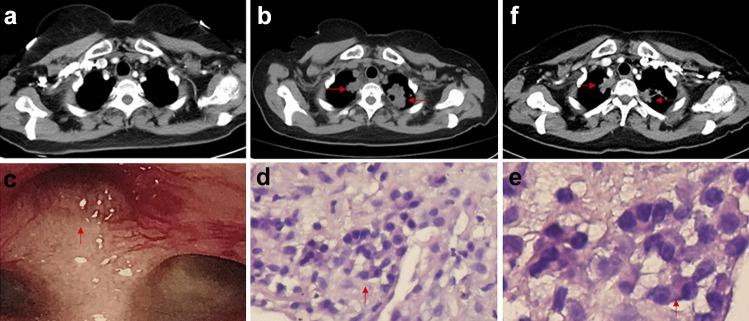

Ceritinib is a new anaplastic lymphoma kinase (ALK) inhibitor that has shown greater potency in patients with advanced ALK-rearranged non-small cell lung cancer, including those who had disease progression in crizotinib treatment. Here we reported, after several months of ceritinib treatment, two patients with advanced ALK-rearranged pulmonary adenocarcinoma exhibited a spectrum of respiratory symptoms like cough and dyspnea, with significantly higher inflammatory indicators. Chest computed tomography (CT) showed multiple bilateral and peripheral lesions in lungs. The prior considerations taken into account were disease progression or infection. However, biopsies of the pulmonary nodules revealed features of granulomatous inflammation without definite cancer cells. We documented for the first time that ceritinib might be associated with pulmonary granulomatous inflammation, and clinicians should be alert to the possibility that the rare adverse event emerged during ceritinib treatment.

塞瑞替尼是一种新型的间变性淋巴瘤激酶(ALK)抑制剂,在晚期ALK 重排的非小细胞肺癌患者中显示出更强的疗效,包括那些在克唑替尼治疗中疾病进展的患者。在这里,我们报告了两名晚期ALK 重排肺腺癌患者在接受塞瑞替尼治疗几个月后出现了一系列呼吸系统症状,如咳嗽和呼吸困难,同时炎症指标显著升高。胸部计算机断层扫描(CT)显示肺部多个双侧和外周病变。先前考虑的因素包括疾病进展或感染。然而,肺部结节的活检显示出肉芽肿性炎症的特征,没有明确的癌细胞。我们首次记录到塞瑞替尼可能与肺肉芽肿性炎症有关,临床医生应该警惕在塞瑞替尼治疗期间出现这种罕见的不良反应的可能性。